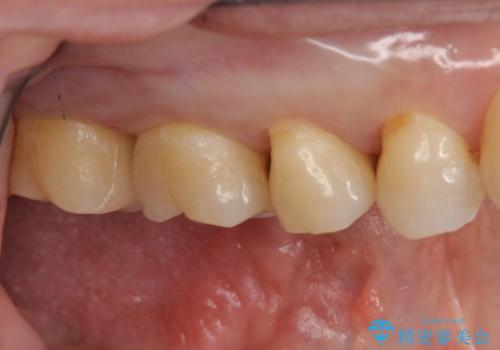

奥歯の虫歯 セラミックインレーによる治療

セラミックインレー装着後は食べ物の詰まりも改善され、お掃除がしやすい環境になりとても満足していただけました。